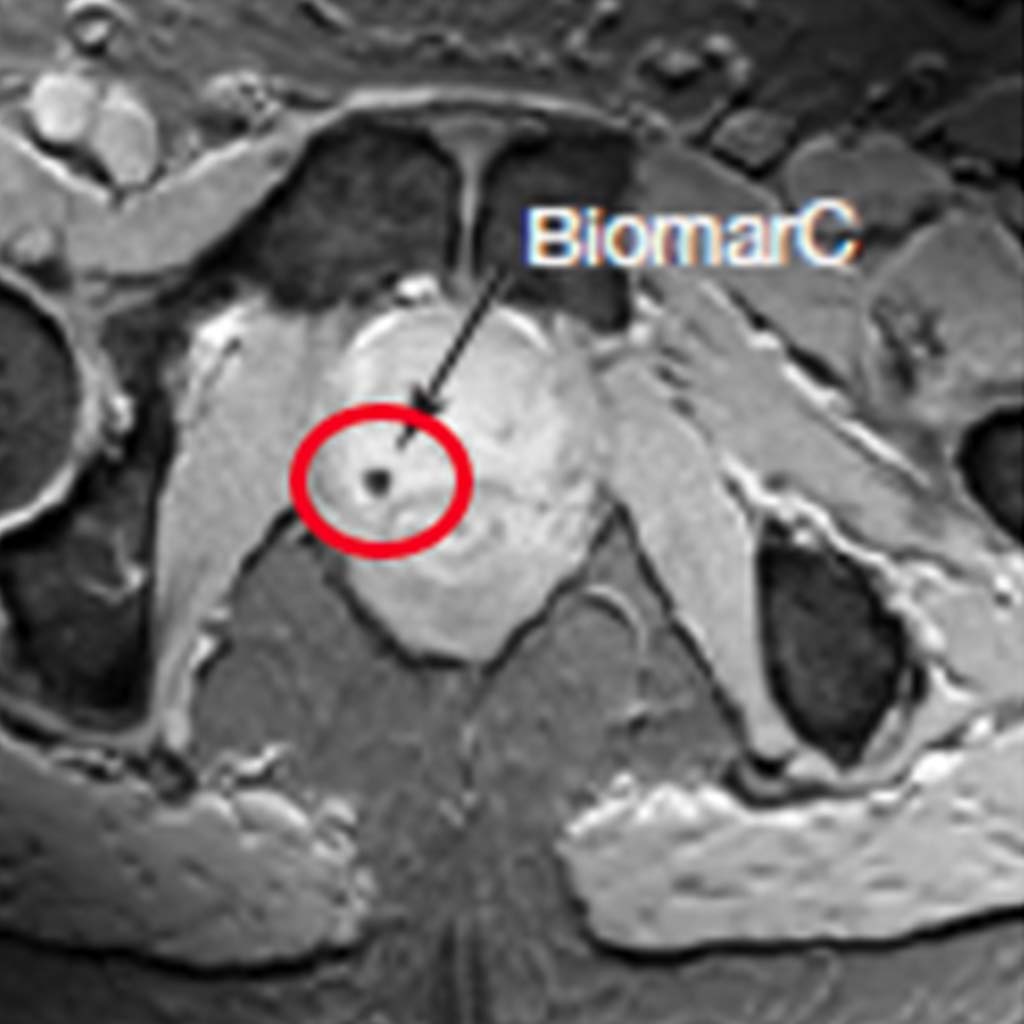

From www.stellarmedical.net

Gold Fiducial Marker Products Stellar Medical Implantable Markers Markers Medical Imaging What are common cancer screening tests? Cancer marker tests in singapore may help patients detect their cancers early and get appropriate treatment. According to the who, early. Cancer markers, such as afp and psa, are crucial in detecting and monitoring cancer through blood,. Cancer screening versus early diagnosis. Today, rapid advancements in medical science have identified a multitude of markers. Markers Medical Imaging.